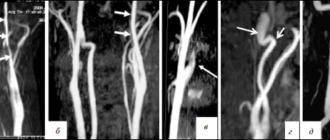

Атеросклероз позвоночной артерии Каждый четвертый инсульт развивается в задних отделах головного мозга в зоне ответственности